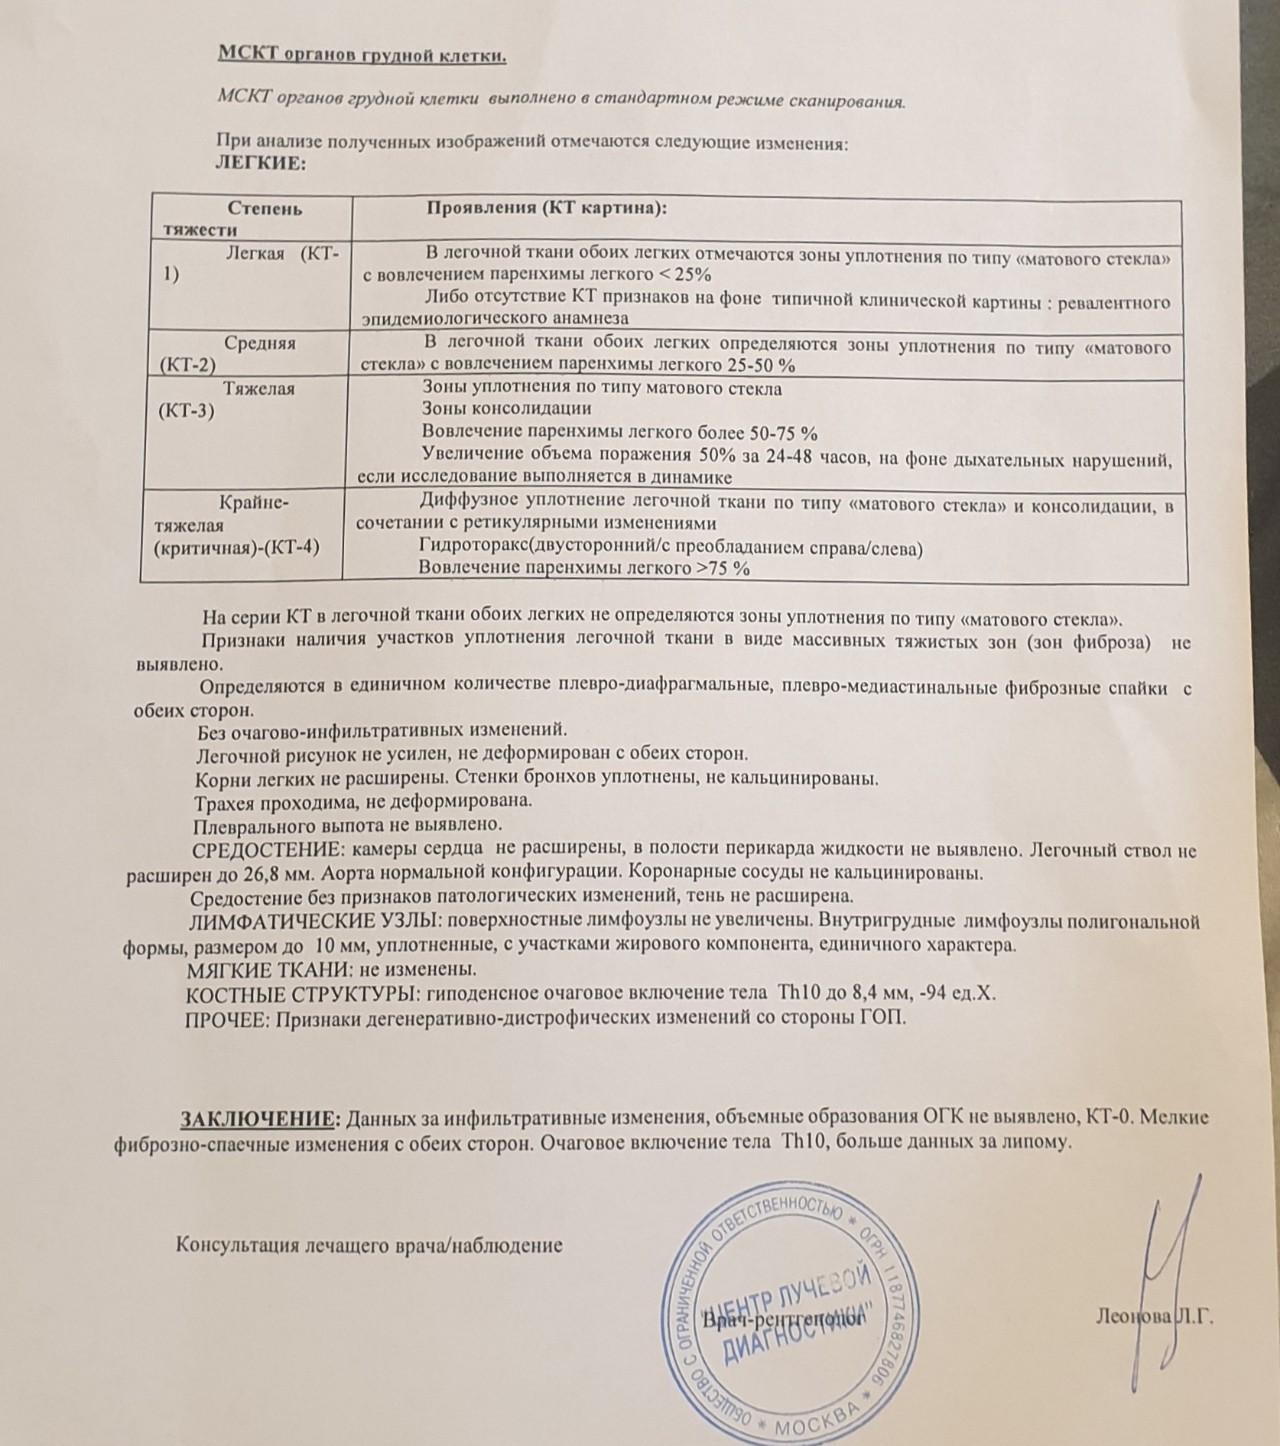

Фото рентгеновских снимков поражения легких при COVID-19

На фотографиях рентгеновских снимков видно, как вирус воздействует на легочную ткань. Характерные признаки поражения легких включают пятна, инфильтраты и наличие жидкости внутри легочных альвеол.

Фото рентгеновских снимков помогают врачам и специалистам визуально определить степень поражения легких и принять соответствующие меры лечения и поддержки пациента.